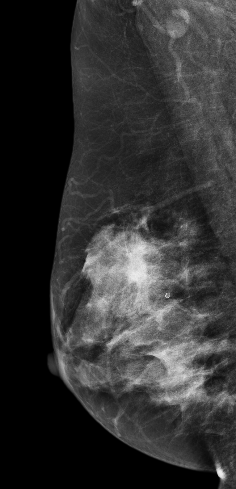

DBT图像:

在常规2DMLO位图像上象限见一较大分叶状肿块影,但在CC位上没有发现明显肿块影像,在V-Preview(合成2D)图像上乳头后方似见不规则密度区,但仍不能明确病变位置,在DBT-plane我们可以乳晕后方清晰见一分叶状肿块影,肿块边缘呈放射状毛刺样改变,亦可见粗大血管影,可以明确肿块大小范围。

影像诊断:

右乳上象限肿块,考虑恶性,BI-RADS 5级。

右乳浸润性癌。